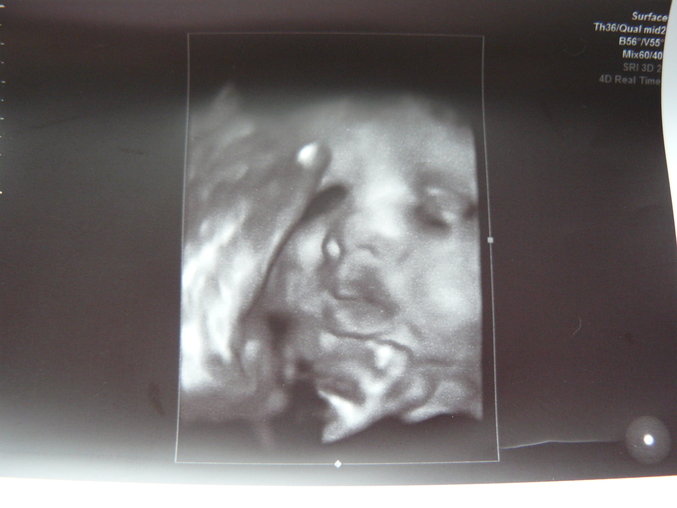

Лирическое отступление))Пока не увидела сегодняшние фото малыша.даже не ёкало внутри!Никаких эмоций по поводу второго ребёнка не было.А сегодня...Этот носик,щечки,губёшки

..Короче,расчувствовалась не на шутку..

..Слава Богу,всё в норме.Единственно - однократное обвитие пуповиной.Моя врач сказала пропить Курантил.Сказала,будем ШМ готовить с 36-ой недели.Она у меня,видите ли,плохая.(Алиску я переносила немного и долго рожала).А вот и фоточка нашей ДЕВОЧКИ!!!(всё-таки,девочки!)..Я снова сомневаюсь,бросьте в меня тапкой.

Прошу прощение за качество.Отсвечивает от глянца..Вот она,губошлёпчатая мордочка!(есть сходство с Алисой).Теперь заказываю коляску и опустошаю магазины. Снова готова терпеть 11 часов..или даже больше.Господи,прошу о здоровье для наших деток.Пусть их появление в наш большой мир будет менее болезненным и светлым.